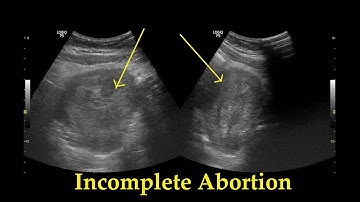

Miscarriage Ultrasound Reporting | Threatened, Missed, Inevitable, Incomplete Types USG Scan Reports